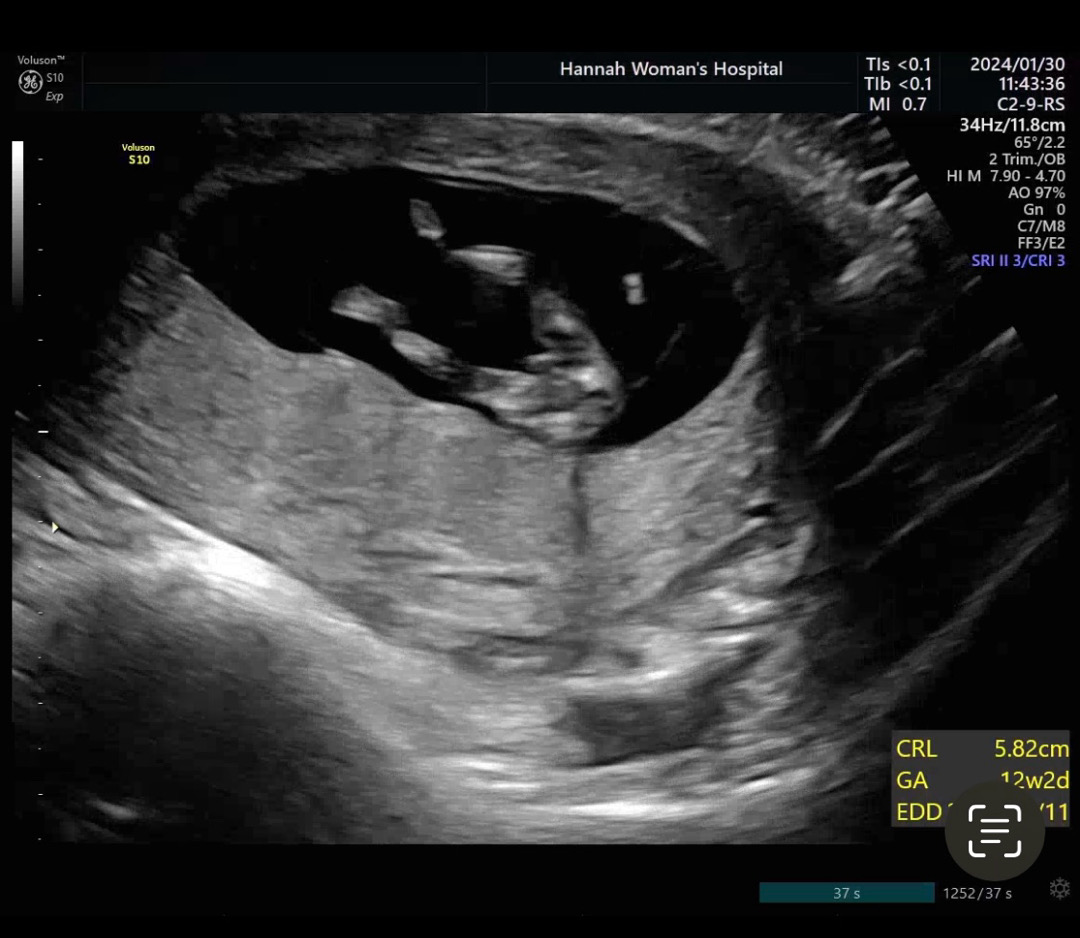

12주0일차 기형아 검사

12주에도 생식기가 보이나요?

12주엔 꼬추든 여자생식기든 똑같구 14주부터 쪼금씩 달라져서 정확한건 16주쯤 정확해져용~

원래 보여요 저게 들어가냐 안들어가냐로 성별이 나뉘는겁니다

어제 어느분이 올린거 보니까 12주에는 둘다 돌출되어 있고 16주는 되야 확실히 알수 있다고 하더라구요!

그래도 대부분 16주에 정확히 정해지니까 아직 안보이는 걸 수도 있어용